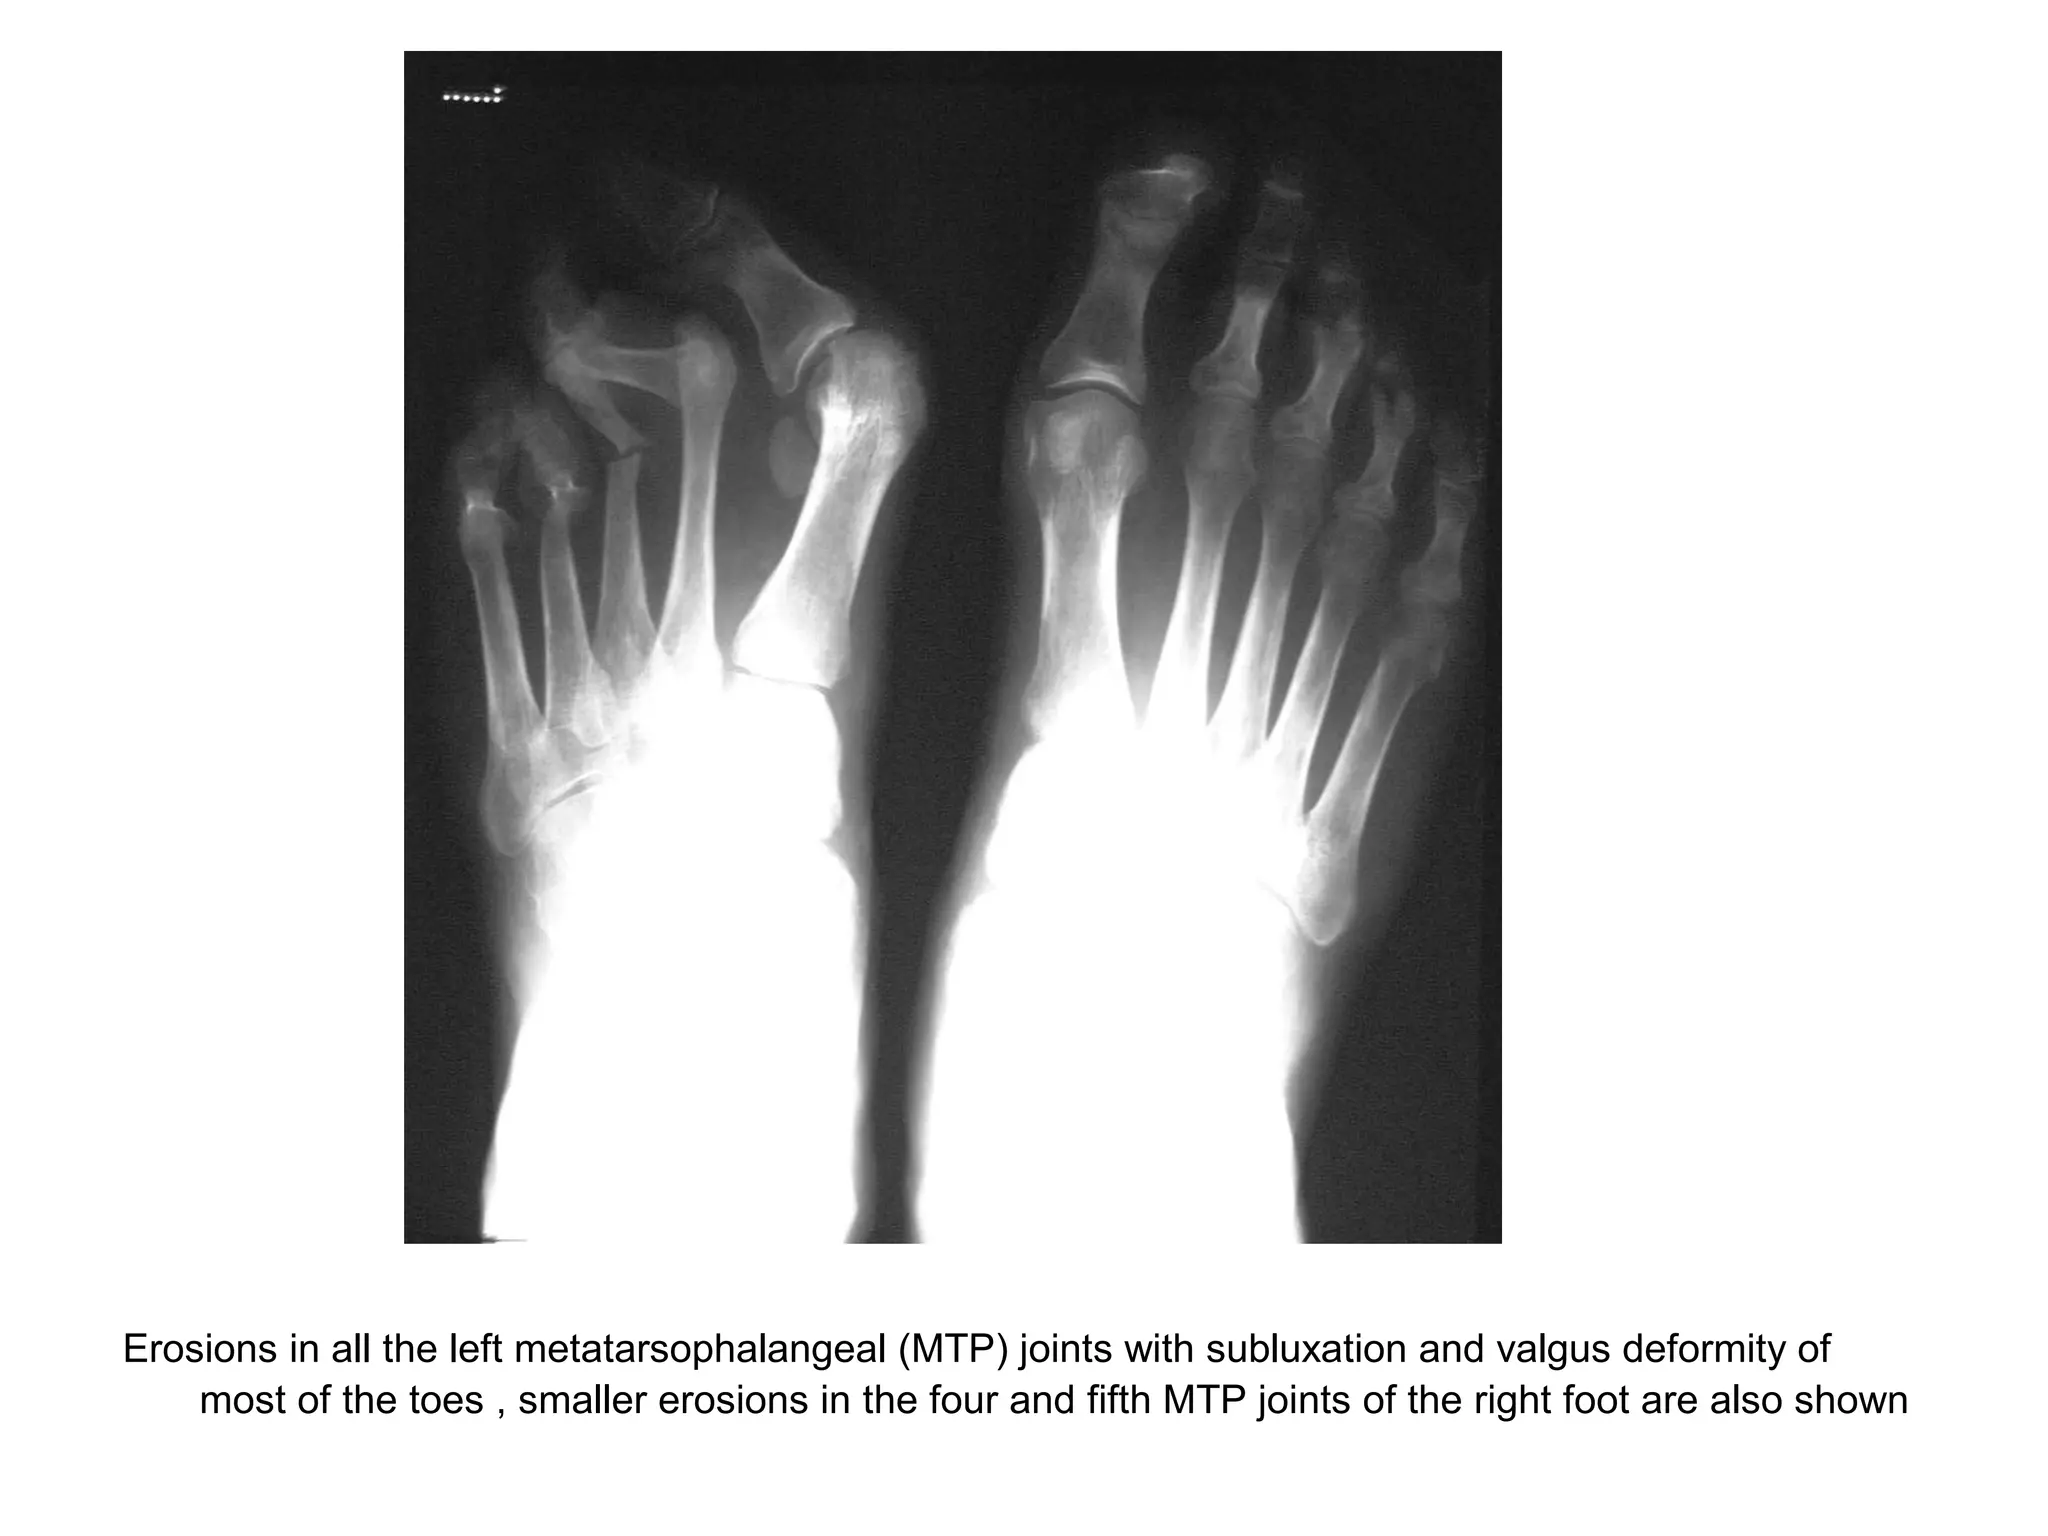

5-RA in the Feet :

-The feet are commonly involved in RA

-Typically the MTP joints in the forefoot and the

talocalcaneonavicular joint in the midfoot are

involved

-Up to 20 % of patients have the MTP joint as the

first site of involvement

Erosions in all the left metatarsophalangeal (MTP) joints with subluxation and valgus deformity of

most of the toes , smaller erosions in the four and fifth MTP joints of the right foot are also shown